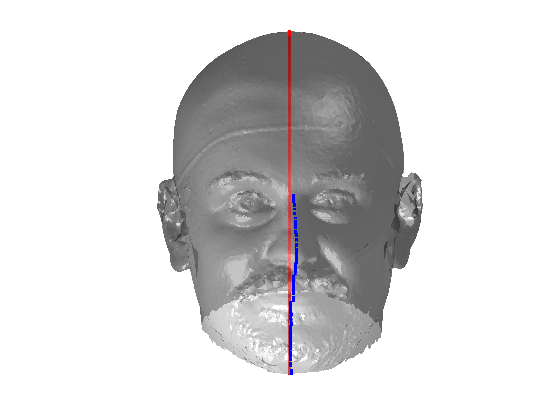

Fig. 9 shows examples of the fitted model (trained on FRGC data) on the first four subjects in our Headspace training set. Note that the mean of the landmarks in the sparse model is centred on the orgin, and so the scan data is moved towards that and becomes frontal in pose. We note that other researchers [28] have used 3D landmark localisation to find the head, but often this only includes landmarks that are relatively easy to localise, namely inner eye corners and nose. Localising more landmarks over a wider facial area has a number of advantage in terms of cropping, pose normalisation and global 3D template warping, all of which are described later.

|

|

|

|